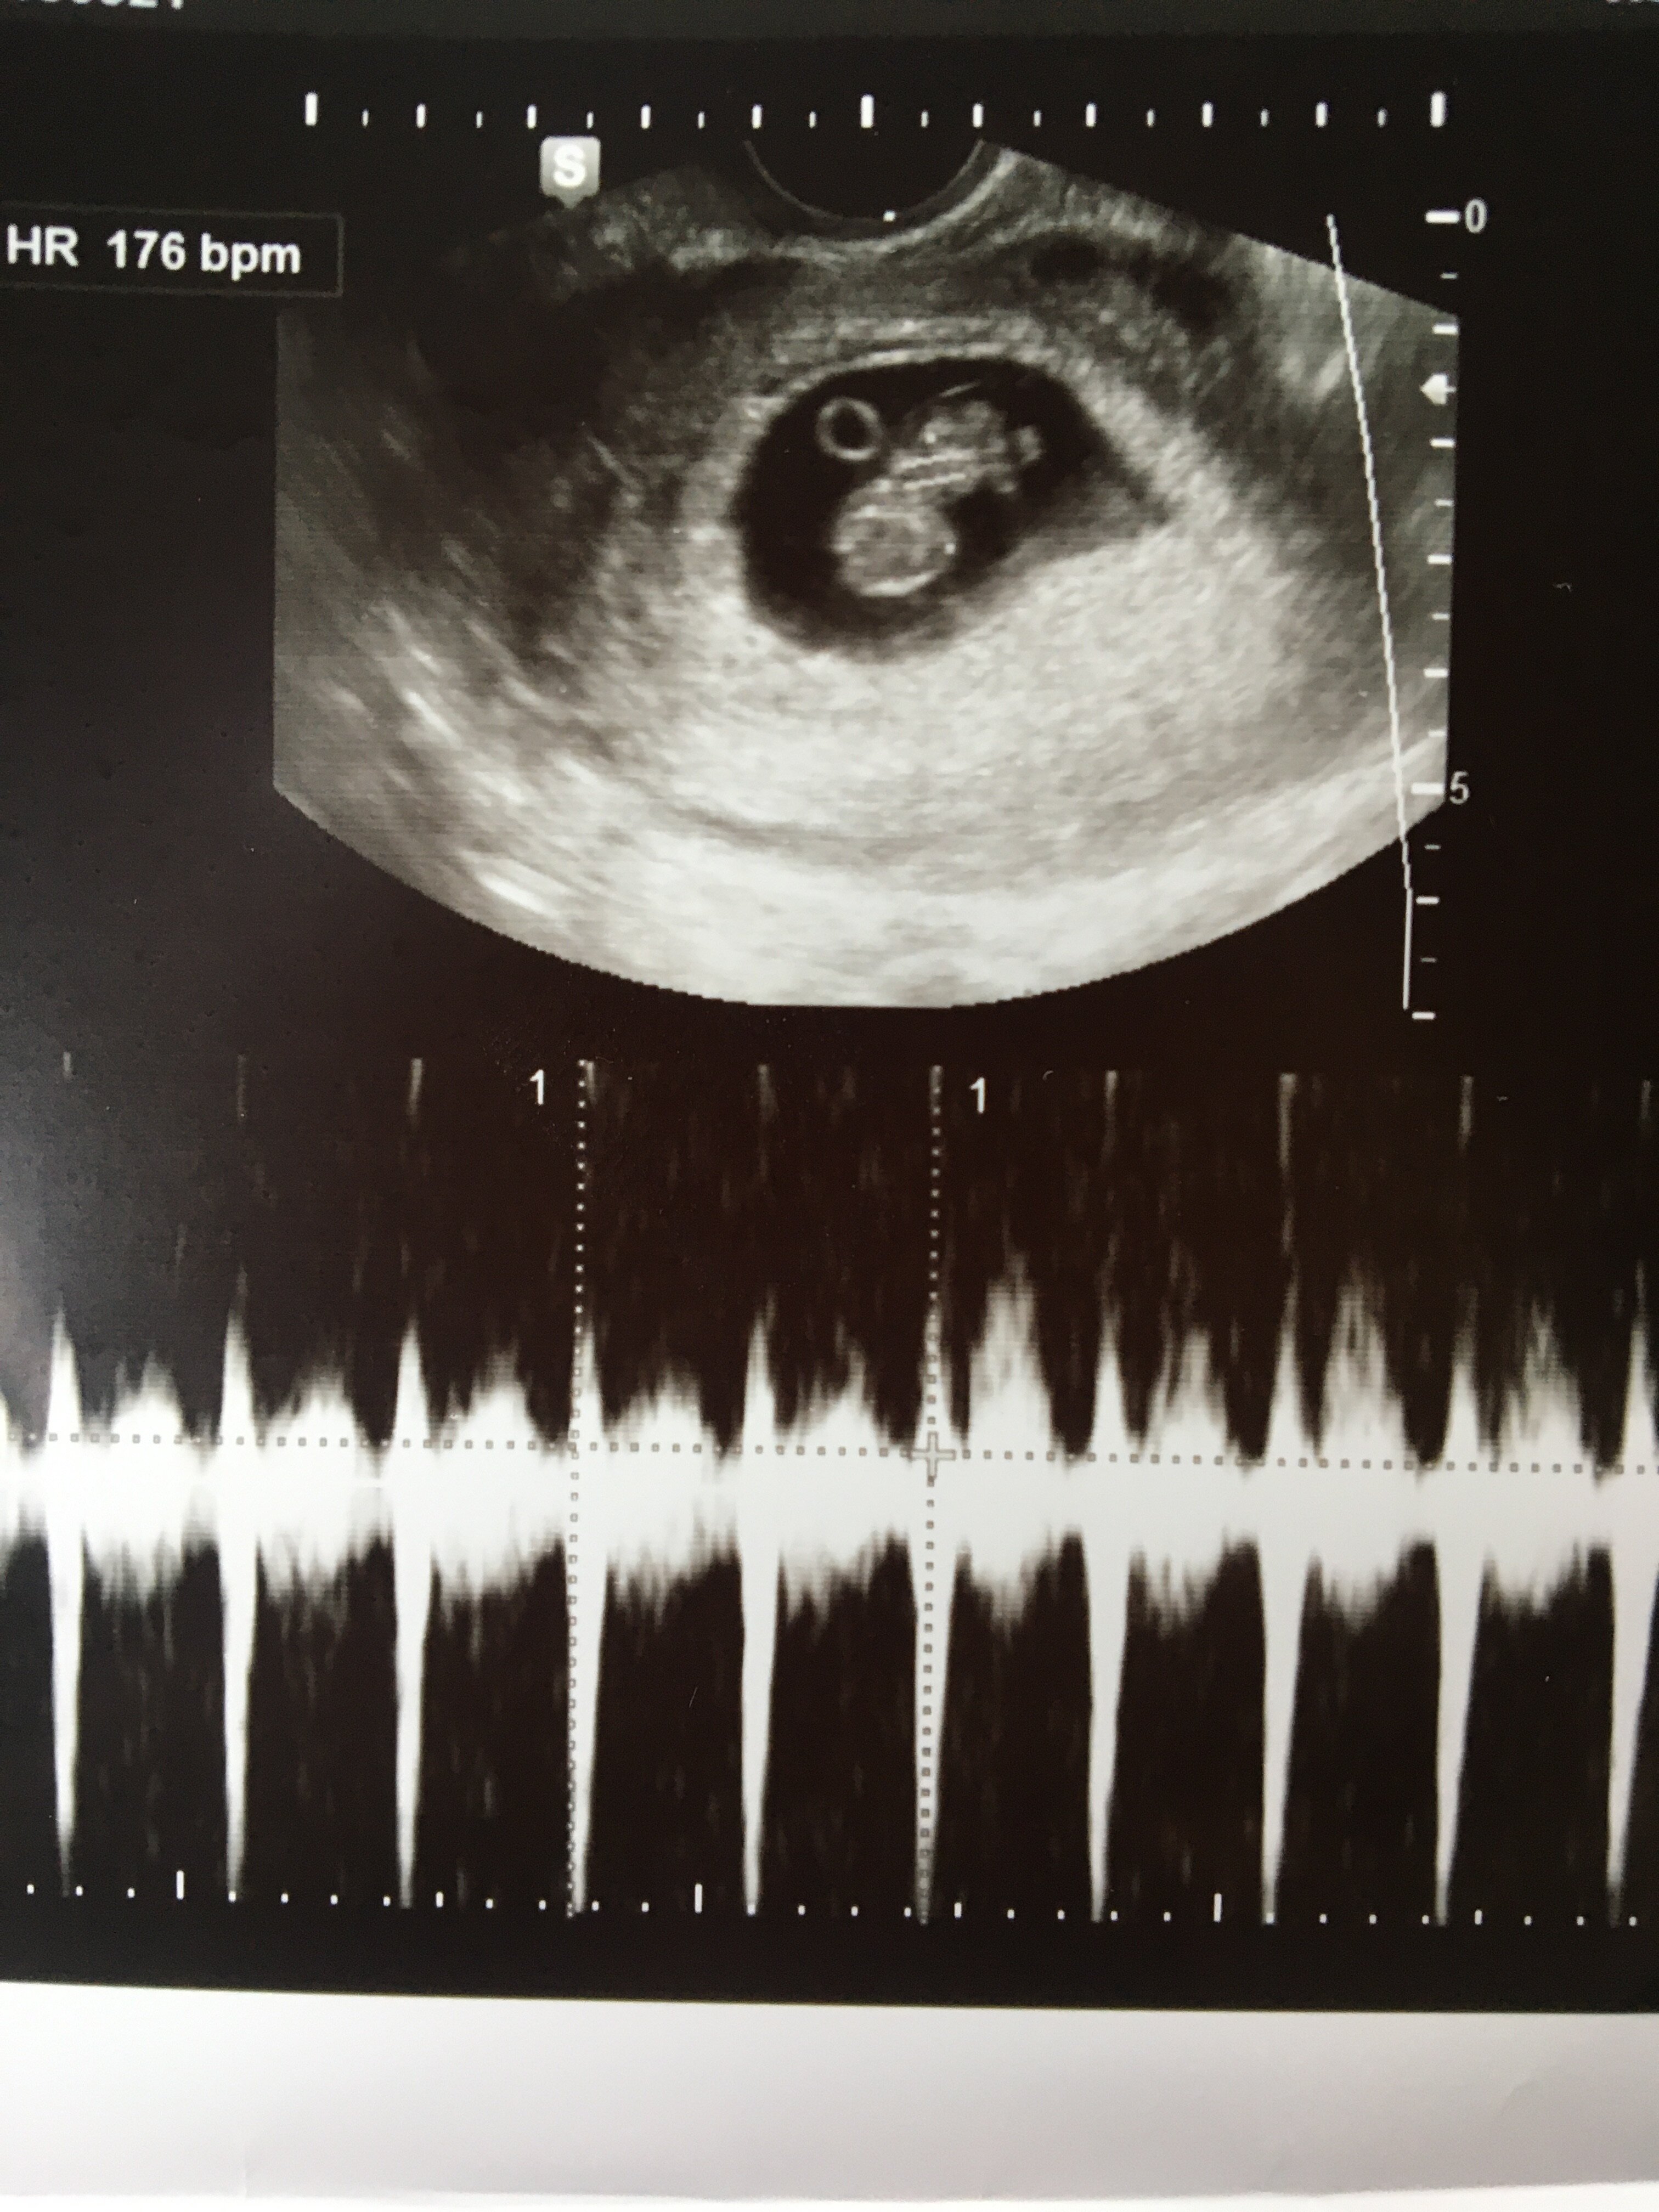

Oooo jaki bobo. Ooo widzę paznokcie. Śliczne. Pokaż wszystkie paluchy hahahHej hej ja po wizycie mamy całe 2.8 cm szczęściadzieciaczek szalał jak niewiem. Lekarz się śmiał ze ruchliwe bedzie serce bije 170. Pogadałam z nim o pappie uspokoił się żeby się nie bała tego testu bo już jedno zdrowe dziecko mam i mi dobrze wychodzi. Na wzdecia powiedział że espunisan mogę brać. Na bol głowy polecił kawę albo pepsi. I powiem wam ze cos w tym jest wczoraj pepsi wypiłam i mnie nie bola głową. A i pooglądaliśmy wszystkie rączki i nóżki nawet palce i stopy i pokazywał.

A oto moje szczęście![]()

Ja już po wizycie, fasolka urosła do 2cm serduszko bije mocno i szybko pierwszy raz je słyszałam